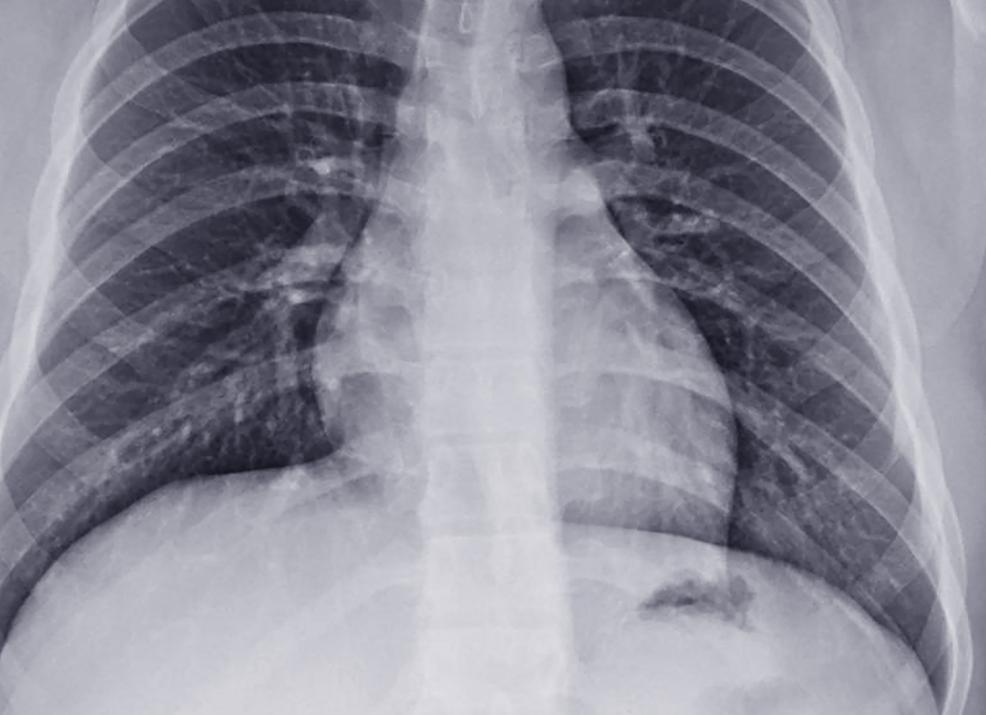

Расшифровка результата ФЛГ: видна ли пневмония?

Так можно ли определить пневмонию по результатам флюорографии грудной клетки? – Да, можно увидеть изменения в лёгких, но главной задачей будет выяснить, чем они вызваны: туберкулезом, онкологией, пневмонией или другими заболеваниями.

Итак, основные рентгенологические симптомы пневмонии:

- очаги воспаления легочных тканей;

- сегментарные (долевые) уплотнения;

- усиление сосудистого рисунка;

- жидкость в плевральной полости;

- расширение и уплотнение «корней» легкого;

- увеличение лимфоузлов;

- фиброз – но это, скорее, показатель ранее перенесенной пневмонии, в результате чего участок легочной ткани замещен тканью соединительной.

В большинстве случаев на ФЛГ наблюдается сразу несколько

симптомов: оценивать их нужно в комплексе, принимая во внимание интенсивность и возможные причинно-следственные связи – тут опыт врача незаменим. Мы лишь вкратце опишем отдельные диагностические нюансы.

Если выявлены очаги воспаления, нужно обратить внимание на их

- размер и количество,

- локализацию,

- контуры (четкие или изрезанные).

При пневмонии видны множественные (не единичные, по крайней мере) инфильтраты в нижних долях легких – чаще всего только с одной стороны, справа. При туберкулезе же процесс обычно двухсторонний, плотные очаги могут располагаться как в нижней, так и в верхней части лёгких. Четкость границы очага позволяет исключить онкологию: дело в том, что контур раковой опухоли обычно нечеткий, «лучистый», несимметричный и изменчивый.

Впервые выявленные сегментарные уплотнения в легких чаще всего говорят о т.н. крупозном воспалении – опаснейшей пневмонии, сопровождающейся интоксикацией организма, затруднением дыхания и сердечно-сосудистой недостаточностью.

Изменение лёгочного рисунка – симптом сам по себе не информативный: он свидетельствует об интенсивном кровоснабжении участка и возникает при любых воспалениях тканей.

Жидкость в плевральной полости может скапливаться как при развитии пневмонии (например, застойной), так и при нарушениях водно-электролитного обмена (их может спровоцировать целый ряд болезней и травм). Для постановки диагноза нужны дополнительные обследования организма.

«Корни» легких (иногда их называют «ворота») – это бронхи, вены, артерии и лимфатическая система. Расширенными они могут быть из-за отека бронхов или сосудов, что, наряду с увеличением лимфоузлов, может говорить о пневмонии или об остром бронхите. Дополнительную информацию даст прослушивание легких (аускультация).

Флюорография, или ФЛГ, представляет собой быстрый и удобный способ диагностики различных заболеваний легких. Показывает ли флюорография пневмонию? За счет того, что в данном методе используются рентгеновские лучи, которые проходят через тело человека и фиксируют особенности тканей, он может легко показать воспалительный процесс в виде затемнений на снимке.

ФЛГ — это метод диагностики нижних дыхательных путей, который заключается в фиксировании изображения органов дыхания человека, через которые проходят рентген-лучи. Из-за того, что ткани органов имеют различные особенности поглощения этих лучшей, на снимке они будут отличаться оттенком. Сердце и бронхи будут светлыми. Легочная ткань должна быть равномерной. Если видны заметные затемнения, можно уверенно говорить о воспалении.

Для того чтобы на снимке определить наличие пневмонии, врач обращает внимание на уплотненные очаги среди инфильтрации и очаги за тенью сердца. Увидев такие признаки, больному назначают дальнейшее обследование, включающее сдачу анализов и прохождение рентгенографии грудной клетки.

Важно понимать, что флюорография не выявляет четкой картины состояния легких. Поэтому иногда выявить некоторые формы пневмонии с помощью ФЛГ невозможно. В этом случае необходимо обращать внимание на присутствие симптомов у больного. Если они указывают на наличие воспалительного процесса, то даже в случае чистой флюорографии больного отправляют на рентген грудной клетки. Лучше всего на снимке ФЛГ распознается инфекционное воспаление легких. Он позволяет врачу четко увидеть признаки и локализацию затемнений легочной ткани.